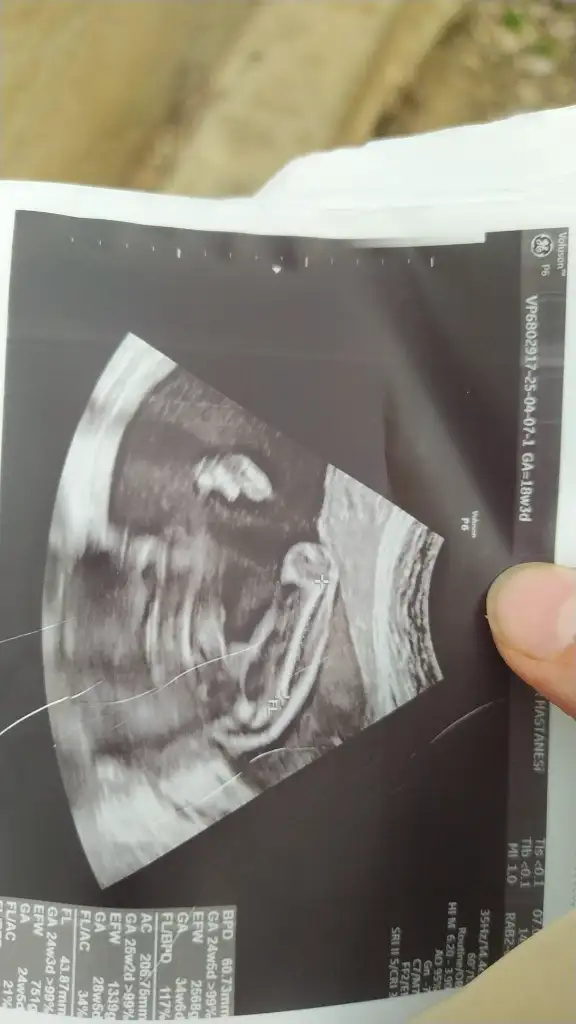

Evet bacak arası doktor yüzde 90 kız dedi yanlız bir cikintida var ama anlamadm diyorBacak arasıysa erkek gibi

Kordon'da olabilir canımEvet bacak arası doktor yüzde 90 kız dedi yanlız bir cikintida var ama anlamadm diyor

Bana da bakar mısınız rica etsemKız gibi görünüyor

Banada bakarmısınız lütfen tahminde bulunurmusunuzKuzum nub gözükmüyor tam o yüzden emin olmamakla birlikte benim kızıma benzettim kız diyim o yüzden